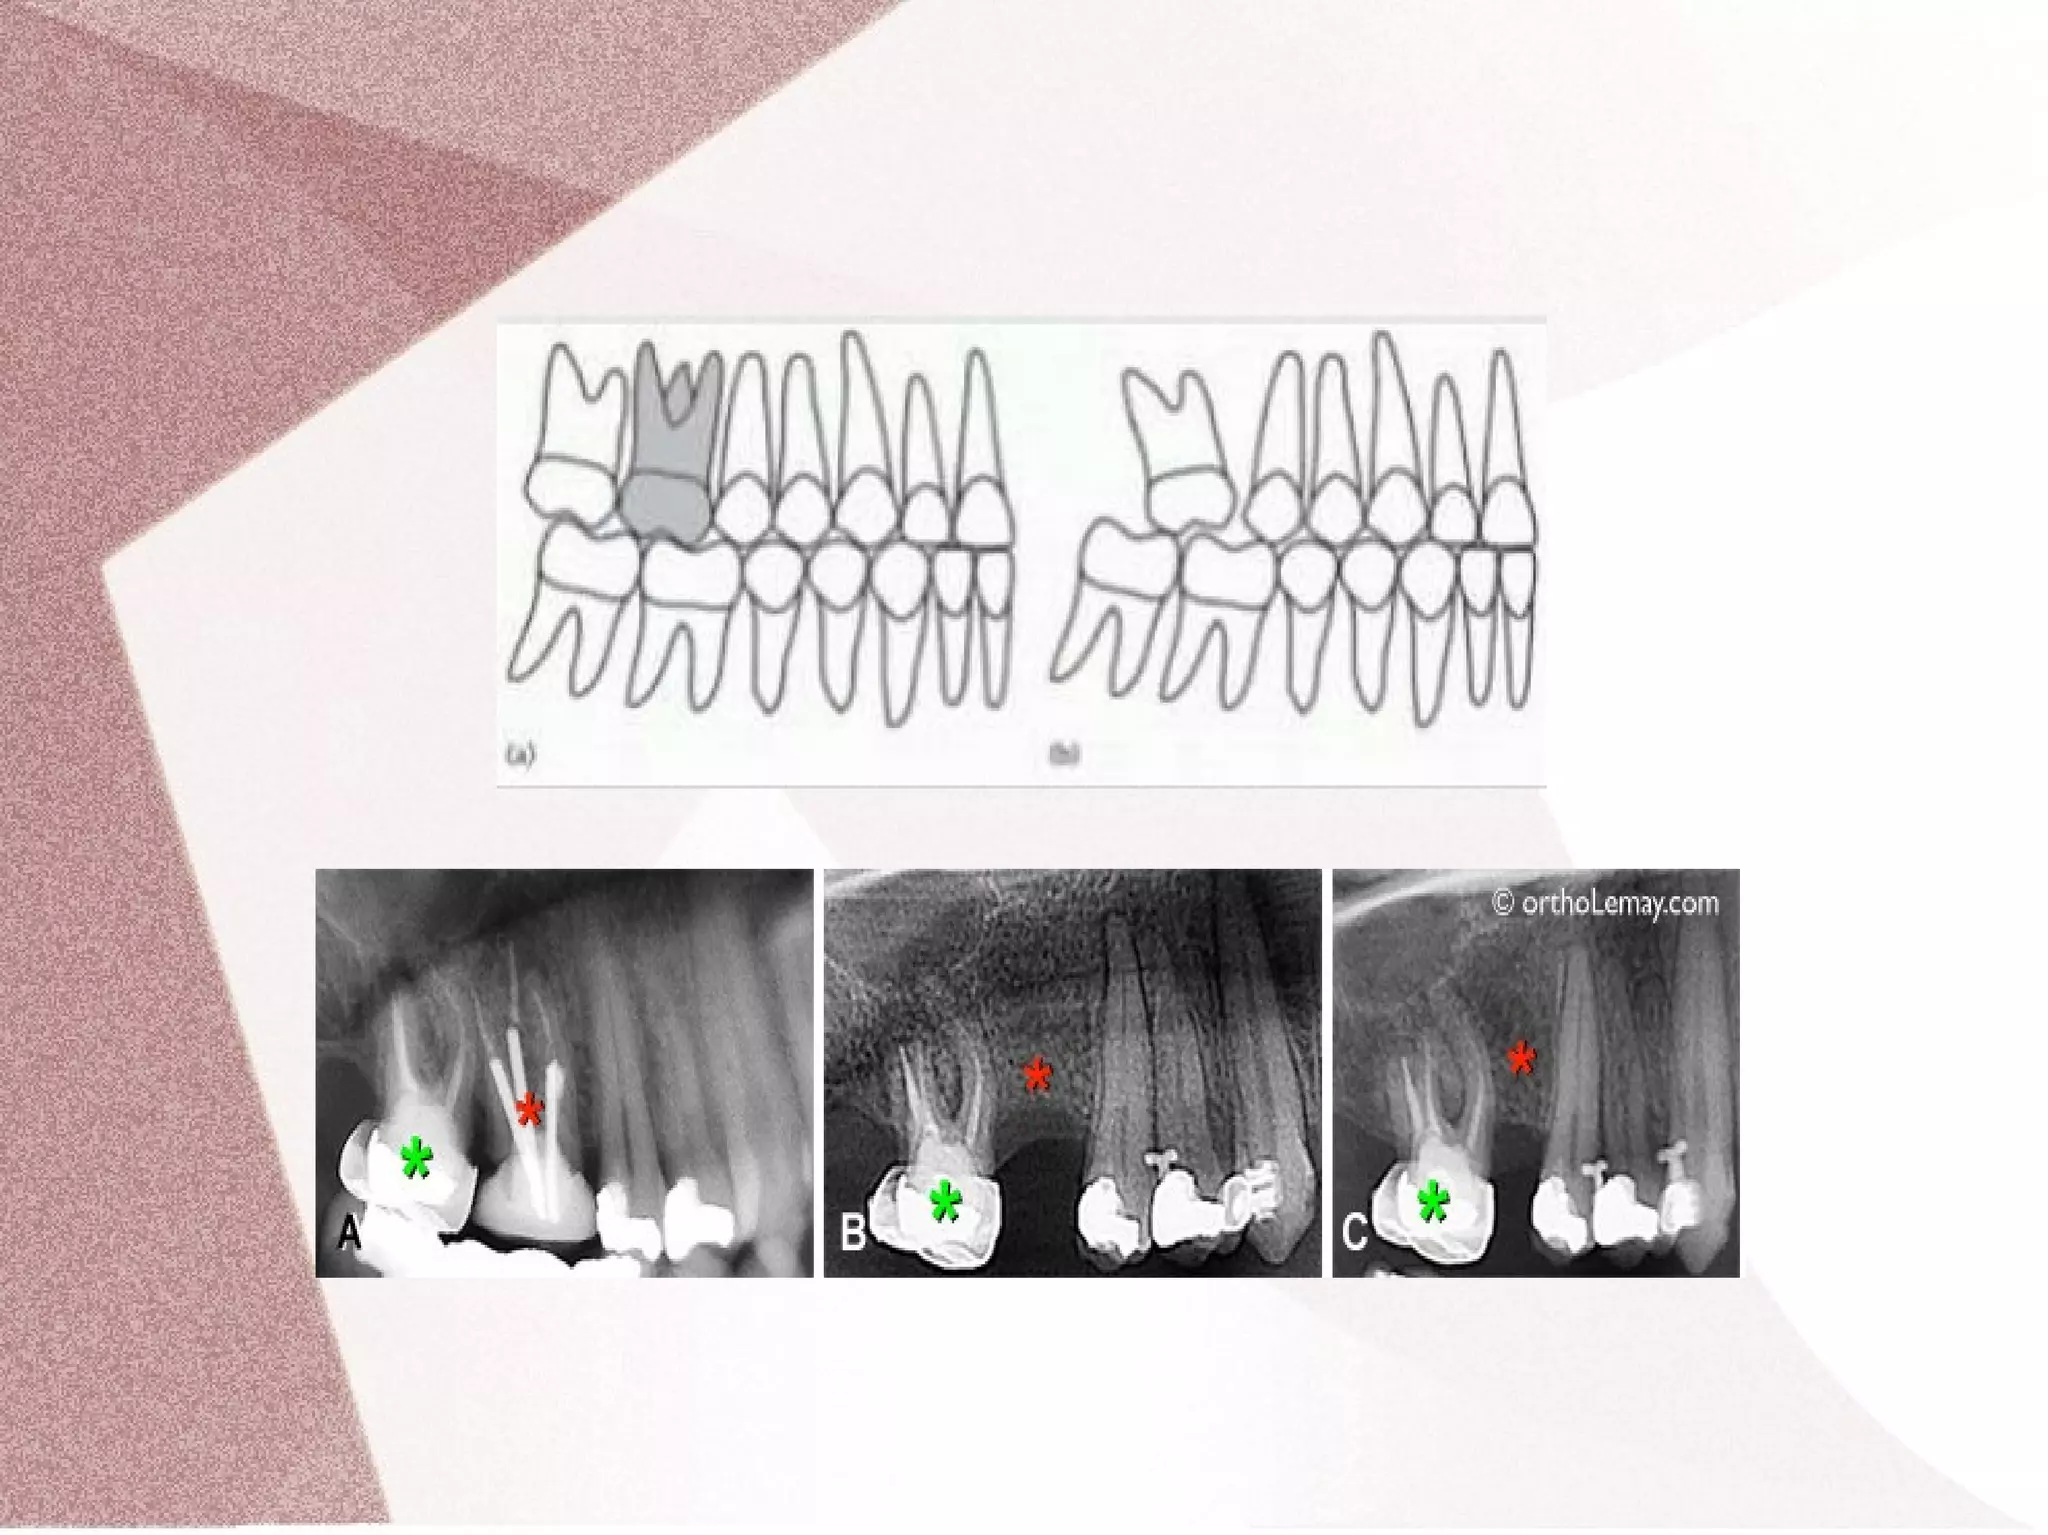

● 1. The loss of only a lower first permanent

molar after the eruption of the lower second

permanent molar (> 8 years) may result in :

(A) Severe mesial tipping of the lower second

permanent molar

(B) Supra-eruption / over eruption of the upper first

(C) Migration or distal tipping of the lower second

premolar